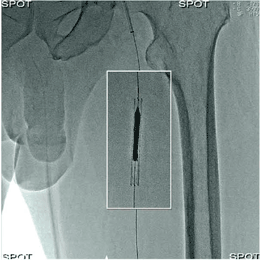

スポット透視では,関心領域にのみX線が照射され,関心領域外には静止画像を表示することで,全体の様子を理解しながら視認が必要な部分にのみリアルタイムのX線透視が可能となる。関心領域は,画像中心に上下・左右対称でなくとも良い。そのイメージ画像を図4に示す。スポット透視の効果については,横須賀共済病院・高橋 淳先生により,心房細動のアブレーションにおいて,スポット透視は効果的に患者面積線量を低減し,術者被ばくを低減する可能性が報告されている4)。

図4 スポット透視(イメージ)

白枠が関心領域。関心領域内はライブ透視,関心領域外は静止画像を表示